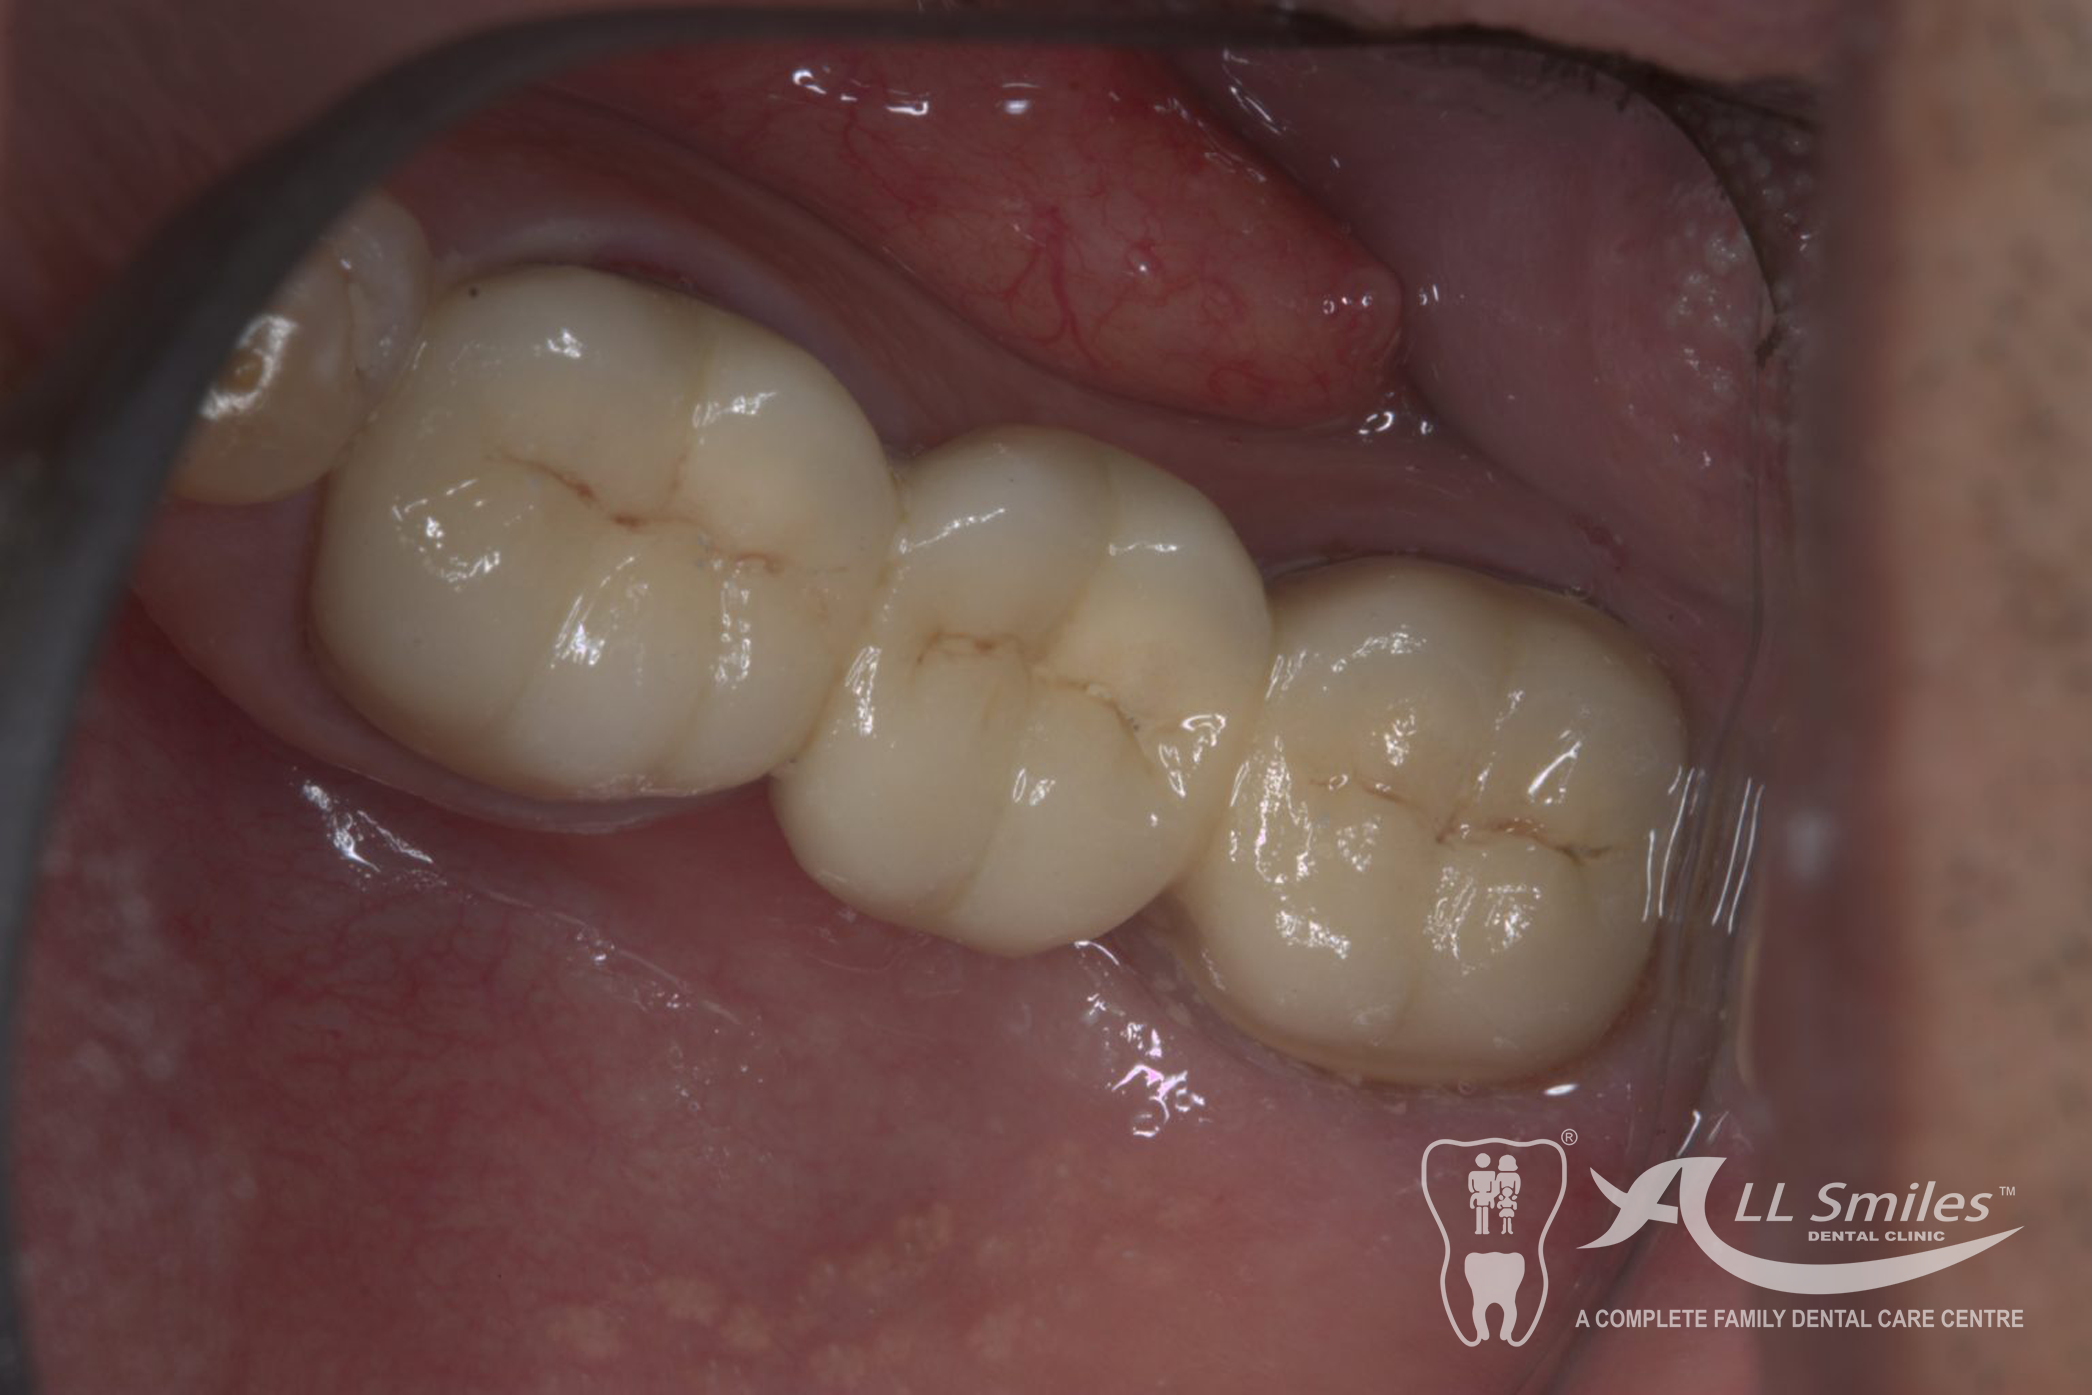

Crowns & Bridges Gallery